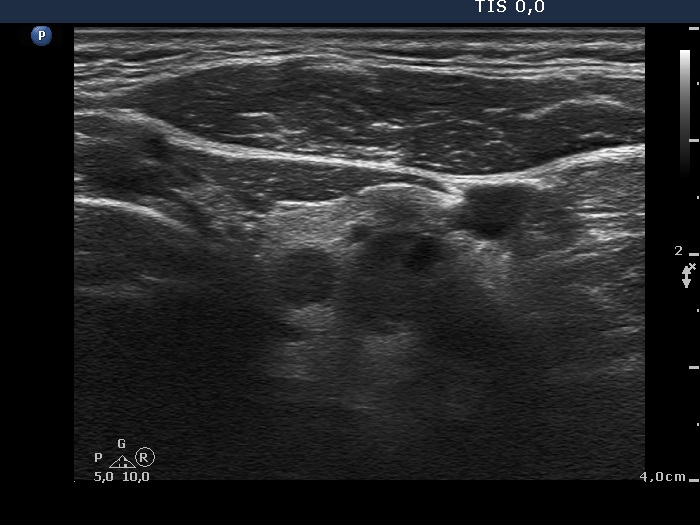

Ultrasonography. The right thyroid was composed of multiple discrete lesions with different echogenicities. The lobe was extremely enlarged with the dimension of 55x65 xminimum 120 mm (width, depth, and length, respectively) and spread retotracheal and substernal. The lower pole of the lobe could not be visualized while swallowing. The left thyroid was normal-sized and contained several hypoechogenic lesions. There was a moderately hypoechogenic nodule in the right lobe. The lesion presented neither halo nor perinodular blood flow.